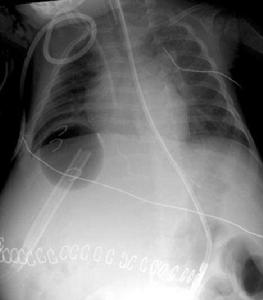

1.腹部B超正常門靜脈結構消失,代之為不規則的彎曲狀血管影,或呈蜂窩狀,其內見血液流動,血流方向無規律;血管壁增厚回聲增強,可見血管內血栓。Ueno依據彩色都卜勒顯像表現將CTPV分為3型:Ⅰ型表現為門靜脈正常結構不清,僅顯示門靜脈區呈蜂窩狀結構,原發性CTPV均屬此型;Ⅱ型表現為門靜脈主幹可以顯示,但內部被栓塞物填塞,在其周圍可見側支靜脈;Ⅲ型表現為門靜脈附近存在腫塊回聲,門靜脈受壓致側支靜脈形成。Ⅱ、Ⅲ型屬繼發性CTPV表現。

(1)門靜脈走行區結構紊亂,正常門靜脈系統結構消失,在門靜脈走行方向上可見由纏繞在一起側支靜脈形成的類似團塊狀軟組織網狀結構,相互之間分界不清,增強掃描後門靜脈明顯強化交織成網、竇隙樣或管樣軟組織結構,在肝門部可見延向肝內門靜脈周圍細條狀密度增高影。

(3)伴門靜脈高壓患者,可在冠狀靜脈、臍旁靜脈、腹膜後腔、肝胃十二指腸韌帶及胃底食管連線區見到迂曲擴張呈匍形走行的側支循環血管,嚴重者迂曲呈團塊狀,增強掃描在門靜脈期示有明顯強化。

3.數字減影血管造影(digitalsubtractionangiography,DSA)主要表現為門靜脈走行區正常門靜脈結構顯示不清,正常門靜脈由不成比例迂曲、呈瘤樣擴張的海綿樣血管代替,顯示為與門靜脈主幹平行、迂曲擴張、呈蛇行的靜脈網,脾靜脈擴張,胃冠狀靜脈及食管靜脈迂曲擴張。